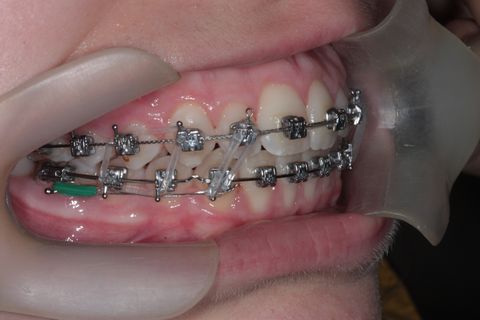

Uso do Twin Force por aproximadamente 3 meses

Twin Force